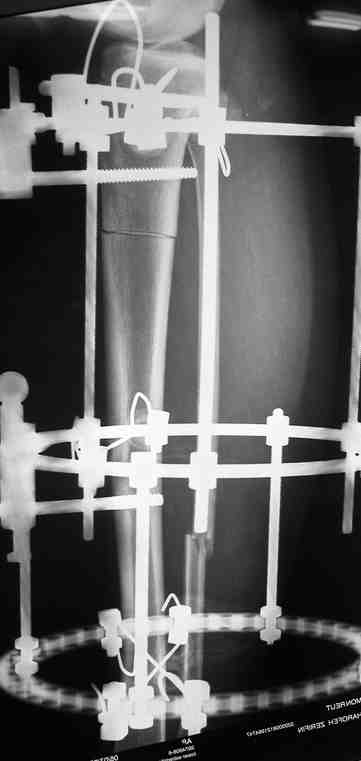

Выше приведены рентгенограммы 13-летнего подростка, страдающего от огнестрельного многооскольчатого перелома дистальной трети бедра. AO наружный фиксатор наложенный в день травмы не дал приемлемой редукции. Через три недели после перелома аппарат Илизарова был наложен без попытки одномоментной репозиции на операционном столе. There are X-Rays of a thirteen year old boy with a comminuted distal femur fracture secondary to a gunshot wound, initially treated with an AO external fixator. The alignment was unacceptable and an Ilizarov external fixator was applied three weeks after the injury. No attempt of definitive reduction was made during the surgery.

Гексаподная приставки наложена на 10 дней и приемлемая редукция была получена. The Hexapod set was applied for ten days and acceptable reduction was received.

По окончанию редукции Гексаподный сет был снят и дальнейшее ведение больного проходило в стандартном режиме аппарата Илизарова. Хороший анатомо-функциональный результат был получен. When reduction was finished, the Hexapod set was removed and further management has been continued by standard Ilizarov regime. Good anatomic and functional results were achieved.